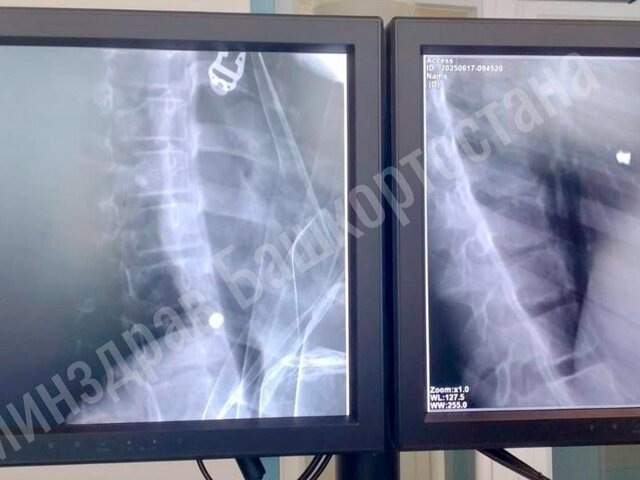

Фото: телеграм-канал "Айрат Рахматуллин"

Скорая доставила ребенка в больницу в тяжелом состоянии с проникающим ранением сердца и травмой легкого. Девочка чувствовала сильную слабость, а также боли при глотании и дыхании.

Врачи Республиканской детской клинической больницы и Республиканского кардиоцентра провели ей торакотомию – операцию по вскрытию грудной клетки. В результате им удалось успешно извлечь пулю.